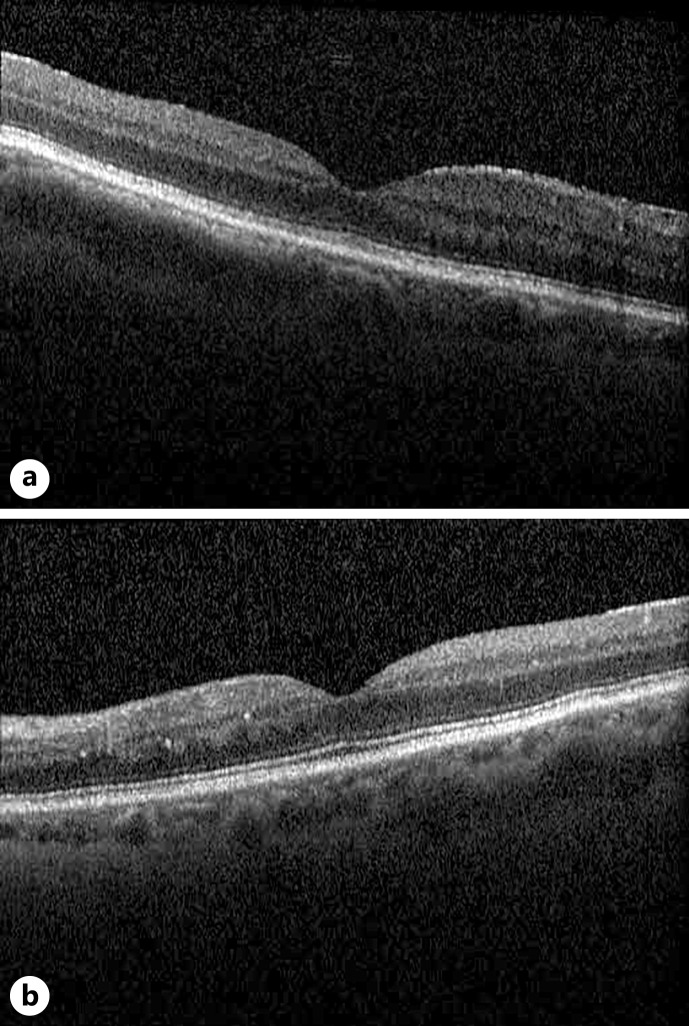

这是一份观察性病例报告,详细介绍了一例新确诊的系统性硬化症患者以双侧渗出性视网膜脱离为表现的硬皮病肾危象。一名 58 岁的女性患者原本身体健康,主要以视力不适为主要症状,经散瞳眼底检查和黄斑 OCT 扫描发现其患有恶性高血压(230/120 mm Hg)和双侧渗出性视网膜脱离。进一步的病史显示她有硬结、轻度吞咽困难和呼吸困难。根据最初的医学检查结果,她被诊断为弥漫性系统性硬化症和斯约格伦综合征,并发硬皮病肾危象。她被送入重症监护室,接受静脉降压治疗,以控制难治性高血压。治疗三个月后,她的视力症状和眼部检查结果均已缓解。由于存在渗出性视网膜脱离和其他高血压视网膜病变的迹象,需要对恶性高血压的潜在病因(包括系统性硬化症)进行彻底的系统筛查。通过紧急降压疗法治疗潜在疾病,解决了渗出性视网膜脱离问题,并恢复了硬皮病肾危象患者的视力。

This is an observational case report to detail a novel case of scleroderma renal crisis presenting as bilateral exudative retinal detachments in a patient with newly diagnosed systemic sclerosis. An otherwise healthy 58-year-old female presented primarily with vision complaints and was found to have malignant hypertension (230/120 mm Hg) and bilateral exudative retinal detachment on dilated fundus examination and macular OCT scan. Further history revealed sclerodactyly, mild dysphagia, and dyspnea. She was diagnosed with diffuse systemic sclerosis and Sjogren's syndrome complicated by an episode of scleroderma renal crisis based on initial medical workup. She was admitted to intensive care for management of refractory hypertension with IV antihypertensive therapy. Three months after treatment, her visual symptoms and ocular findings resolved. The presence of exudative retinal detachment among other signs of hypertensive retinopathy warrants thorough systemic screening for underlying causes of malignant hypertension, including systemic sclerosis. Treatment of the underlying disease with urgent antihypertensive therapy resolved the exudative retinal detachments and restored vision in the case of a scleroderma renal crisis.